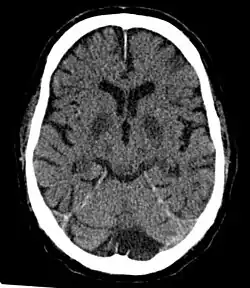

Im Gehirn sind bei Hypoxie bestimmte Bereiche besonders betroffen, die Nervenzellschäden treten in diesen Regionen zuerst auf. Dazu gehören die Purkinje-Zellen des Kleinhirns und der CA1-Bereich des Ammonshornes. Die Zellen reagieren auf die äußeren Einflüsse mit der Aktivierung sogenannter Hitzeschockproteine. Diese und weitere Produkte aus der c-Fos- und c-Jun-Proteinfamilie ändern bestimmte Zellfunktionen, die das Überleben oder das kontrollierte Absterben der Zellen regulieren sollen.

Morphologisch beobachtet man in geschädigten Bereichen des Gehirns Nekrosen, Schrumpfungen des Hirnmantels und vor allem einen selektiven Untergang der Neuronen. Letztere schrumpfen zu einem charakteristischen Dreieck mit homogenem Aussehen zusammen und können von Pathologen unter dem Mikroskop diagnostiziert werden.